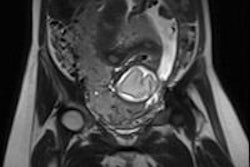

![]()  |

| Axial T2-weighted MR image shows signal intensity of peritoneal inclusion cyst (solid arrowheads) appears to be brighter than that of ovarian cysts. Note left ovarian simple cyst and right ovarian follicle (open arrowheads). Toprak U, Pasaoglu E, Karademir MA, Gulbay M, "Sonographic, CT, and MRI Findings of Endometrial Stromal Sarcoma Located in the Myometrium and Associated with Peritoneal Inclusion Cyst," (AJR 2004 182; 1531-1533). |